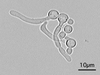

How does Sporothrix schenckii exist in the human body and in the soil?

Cigar-shaped yeast in the human body at 37°C; hyphae with spores in soil (conidia); S schenckii is dimorphic